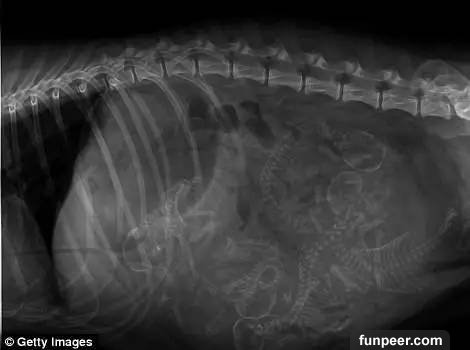

豚鼠的整個身體似乎都擠滿了孩子